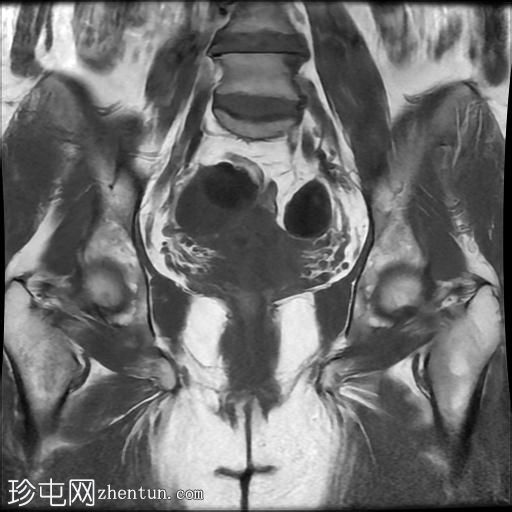

冠状位

T1加权像

右侧输卵管呈管状囊性扩张,直径达30 mm,提示输卵管积水,呈均匀液体信号,无实性成分。

左侧输卵管亦有轻度扩张,直径26 mm,符合输卵管积水表现。

右侧卵巢可见一单纯性卵巢囊肿,大小约35 x 40 mm,呈正常液体等效信号。

宫内节育器位置正常。

MRI 检查结果显示双侧输卵管积水和右侧卵巢单纯性囊肿。总体而言,所有附件和盆腔检查结果均显示良性 MRI 特征(O-RADS 2 类),无恶性肿瘤迹象。